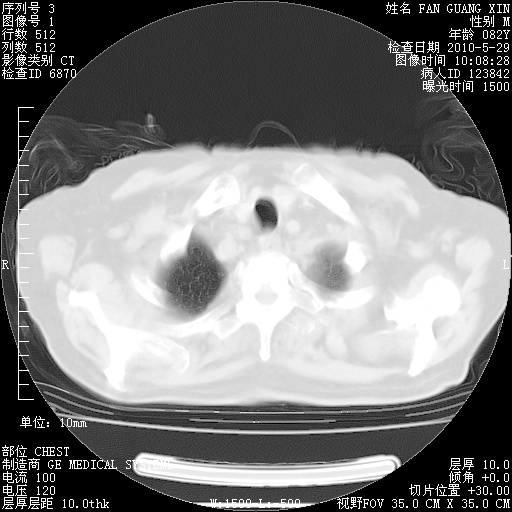

治疗3周后的肺部CT纵隔窗

再治疗10天后的肺部CT